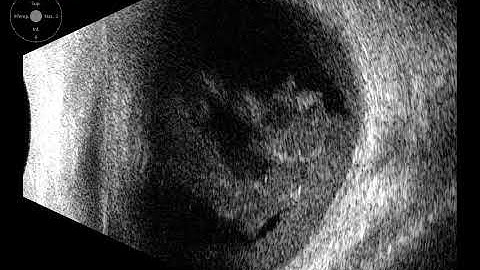

RIGID PMMA PCIOL RESCUE FROM VITREOUS CAVITY - APPROACH WHEN NO VR SETUP - Dr Saurav Piya